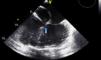

Transesophageal echocardiography showing insertion of the atrioventricular valves in the same plane (arrow), consistent with congenitally corrected transposition of the great vessels and atrioventricular septal defect, an association that occurs in 75% of cases2 (Video 3).

Transesophageal echocardiography showing right atrium receiving two venae cavae; morphologically mitral atrioventricular valve in right position; lead (white arrow) identifying the superior vena cava and morphologically left ventricle in right position; atrial septal defect with residual low shunt (blue arrow) (Videos 4 and 5).